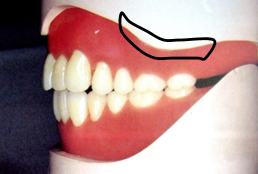

6.磨牙后垫(retromolar pad)

位于下颌最后磨牙牙槽嵴远端的粘膜软垫,覆盖在磨牙后三角上,由疏松的结缔组织构成,含黏液腺。

磨牙后垫的形态和位置比较稳定,作为排人工牙时的解剖标志;垂直向:下颌第一磨牙的颌平面与磨牙后垫的1/2处等高;

前后向:下颌第二磨牙应位于磨牙后垫前缘;

颊舌向:磨牙后垫颊面、舌面向前与下颌尖牙的近中面形成一个三角形。